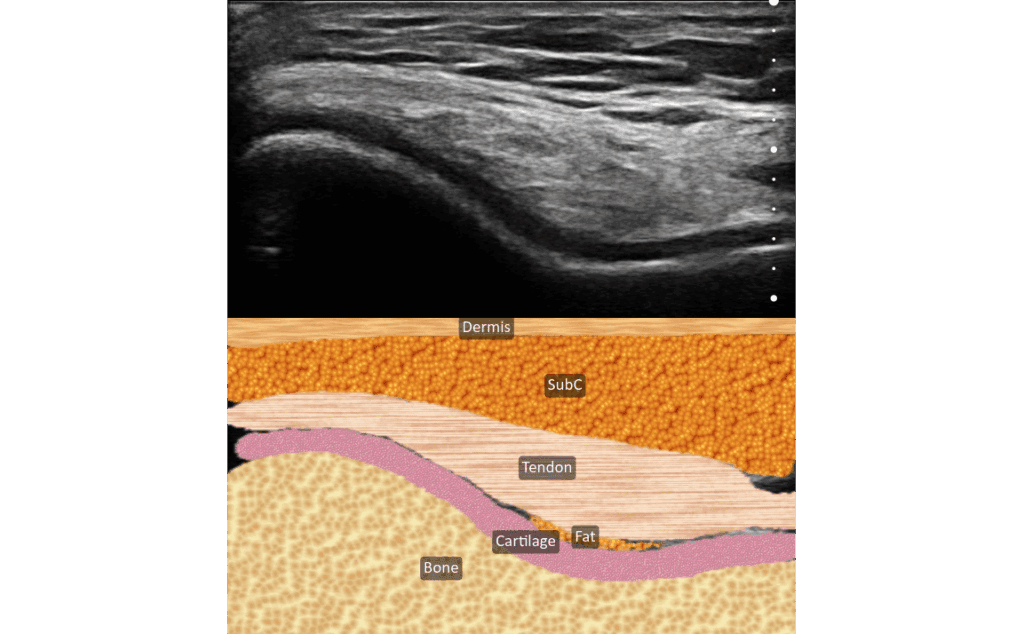

The beautiful thing about ultrasound is you see the needle and you see the medication and you see how it spreads within the tissue.